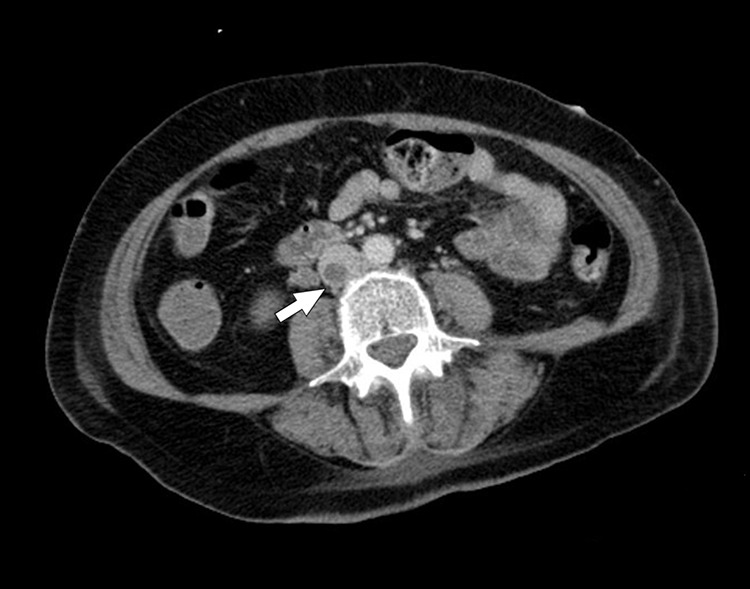

椎管旁类固醇注射,虽然广泛用于治疗背痛,但有严重并发症的风险,包括感染。我们描述了一位54岁的免疫功能正常的女性,她在腰椎棘旁类固醇注射治疗背痛后发生了弥散性耐甲氧西林金黄色葡萄球菌(MRSA)感染。患者表现为发热、呼吸困难和急性腰痛,进展为缺氧性呼吸衰竭,需要插管。诊断结果显示MRSA菌血症并发腰椎硬膜外脓肿、双侧腰肌和腰方肌化脓性炎、下腔静脉(IVC)脓毒性血栓性静脉炎、肺脓毒性栓塞和脑膜脑炎。患者接受静脉注射万古霉素和阿哌沙班抗凝治疗。在完成8周的疗程后,观察到临床改善,菌血症消退,下腔静脉血栓放射学完全消退。该病例强调了MRSA在其强大毒力因素的驱动下,将局部感染转化为广泛转移性疾病的破坏性潜力。它指出了早期识别系统性并发症的重要性,包括血管血栓形成和中枢神经系统受累,在椎管旁干预后。此外,它表明需要及时成像,及时施用靶向抗生素和多学科管理。鉴于越来越多地使用皮质类固醇注射和对抗生素耐药病原体的日益关注,该病例提醒人们注意潜在的医源性并发症以及感染控制和警惕监测的至关重要性。即使没有明显的免疫抑制,临床医生也应该对注射类固醇后出现全身性症状的患者保持高度怀疑。

Paraspinal steroid injections, while widely employed for the treatment of back pain, carry risks of serious complications including infection. We describe a 54-year-old immunocompetent woman who developed a disseminated methicillin-resistant Staphylococcus aureus (MRSA) infection following a lumbar paraspinal steroid injection for back pain. She presented with fever, dyspnea, and acute low back pain, progressing to hypoxic respiratory failure requiring intubation. Diagnostic workup revealed MRSA bacteremia complicated by a lumbar spinal epidural abscess, bilateral psoas and quadratus lumborum pyomyositis, inferior vena cava (IVC) septic thrombophlebitis, pulmonary septic emboli, and meningoencephalitis. The patient received intravenous vancomycin and anticoagulation therapy with apixaban. Clinical improvement was observed with resolution of bacteremia and complete radiological resolution of the IVC thrombus after completing an 8-week treatment course. This case underscores the devastating potential of MRSA to transform a localized infection into widespread metastatic disease, driven by its potent virulence factors. It points out the importance of early recognition of systemic complications, including vascular thrombosis and central nervous system involvement, following paraspinal interventions. Moreover, it demonstrates the need for prompt imaging, timely administration of targeted antibiotics, and multidisciplinary management. Given the increasing use of corticosteroid injections and rising concerns about antibiotic-resistant pathogens, this case serves as a reminder of potential iatrogenic complications and the critical importance of infection control and vigilant monitoring. Clinicians should maintain a high index of suspicion for deep-seated infections in patients presenting with systemic symptoms after steroid injection, even in the absence of overt immunosuppression.